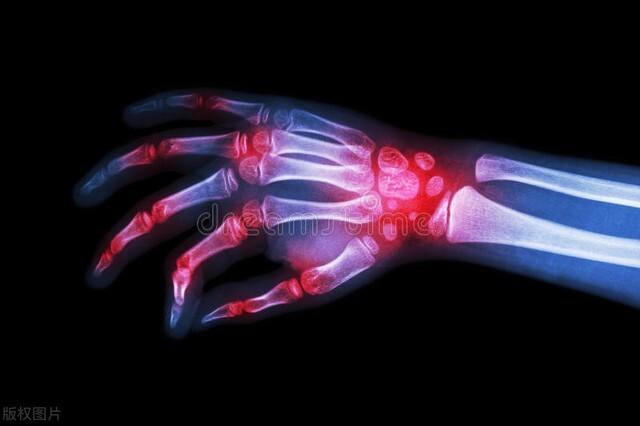

类风湿关节炎导致的手指僵硬!其实在我们的日常生活当中,只要提及手指僵硬、疼痛的话,大部分的人群考虑的还是类风湿关节炎。类风湿关节炎这种疾病会慢慢的破坏整个关节的软骨,造成关节周边的肿胀,关节严重的畸形,而且由于类风湿关节炎导致的手指僵硬、疼痛持续的时间会很长,早上起来要活动超过30分钟以上,甚至要几个小时才能慢慢的有所缓解。

而且这种症状如果不给予控制会越来越重,而且会累积多个关节,有些患者手指出现症状以后慢慢的长趾关节,腕关节,膝关节,肘关节等多个关节也会开始出现类风湿的改变。应对:

●想要明确存在类风湿关节炎的话,需要进行类风湿相关方面的血化验,对于手指关节的可疑类风湿关节炎要进行x线检查,在类风湿关节炎的x线片上,我们能看到典型的关节软骨破坏,关节骨破坏以及严重的骨质疏松。和普通的骨关节炎还是能够做出鉴别诊断的。●对于类风湿手指关节炎的治疗是一个全身性的治疗,要在风湿免疫科医生的指导下科学系统的用药,手指症状如果明显的话,也可以考虑外用非甾体抗炎镇痛药。

这是一种免疫性疾病,主要发生于多个小关节,初期可见于手指关节,出现疼痛,肿胀,僵硬手指僵硬以晨起时明显,通过自己慢慢活动可逐渐减轻。后期随着病情的发展可以出现多个关节受累,甚至出现明显的关节畸形。

一般查类风湿因子可成阳性表现,应该早期发现,早期治疗。

类风湿性关节炎 是一种以关节病变为主的慢性全身自身免疫性疾病,典型症状,起病隐匿,通常是从近端手指指间关节、掌指关节、手腕等小关节最先起病,逐渐表现为对称性多个关节受累,最终由典型的关节炎症性病变,如手指长时间晨僵、肿胀、疼痛等,可导致关节严重畸形。检查方面可以根据抗环瓜氨酸肽抗体、类风湿因子、抗土变形瓜氨酸波形蛋白抗体、抗核周因子和隐形类风湿因子等抗体的阳性明确诊断。对症服用非甾体抗炎药缓解疼痛症状,服用抗风湿药物改善病情,主要就是一个早期治疗,规范治疗,定期监测和随访的原则。非急性期可以热水浴热疗放松肌肉,急性期可以冰敷缓解疼痛,不能进行热疗。平时生活中也要注意改变不良生活习惯,减轻关节的负担,减少关节损伤,控制症状。

一、类风湿性关节炎,出现上面这个症状,首先考虑的是它。类风湿性关节炎是一种自身免疫性疾病,发病原因尚不太清楚,女性多发,比男性高2-3倍,常见于40-60岁人群。往往是在早上起来的时候容易出现,活动一会能够有所改善。有些还有指关节变形,或者皮下有结节,或者有低热。常表现为双侧手指关节僵硬肿胀。根据美国风湿病协会1987年的诊断标准:

6、手X线片改变(至少有骨质疏松和关节间隙的狭窄);